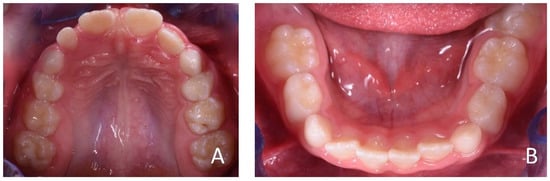

3.1. Clinical Case #1